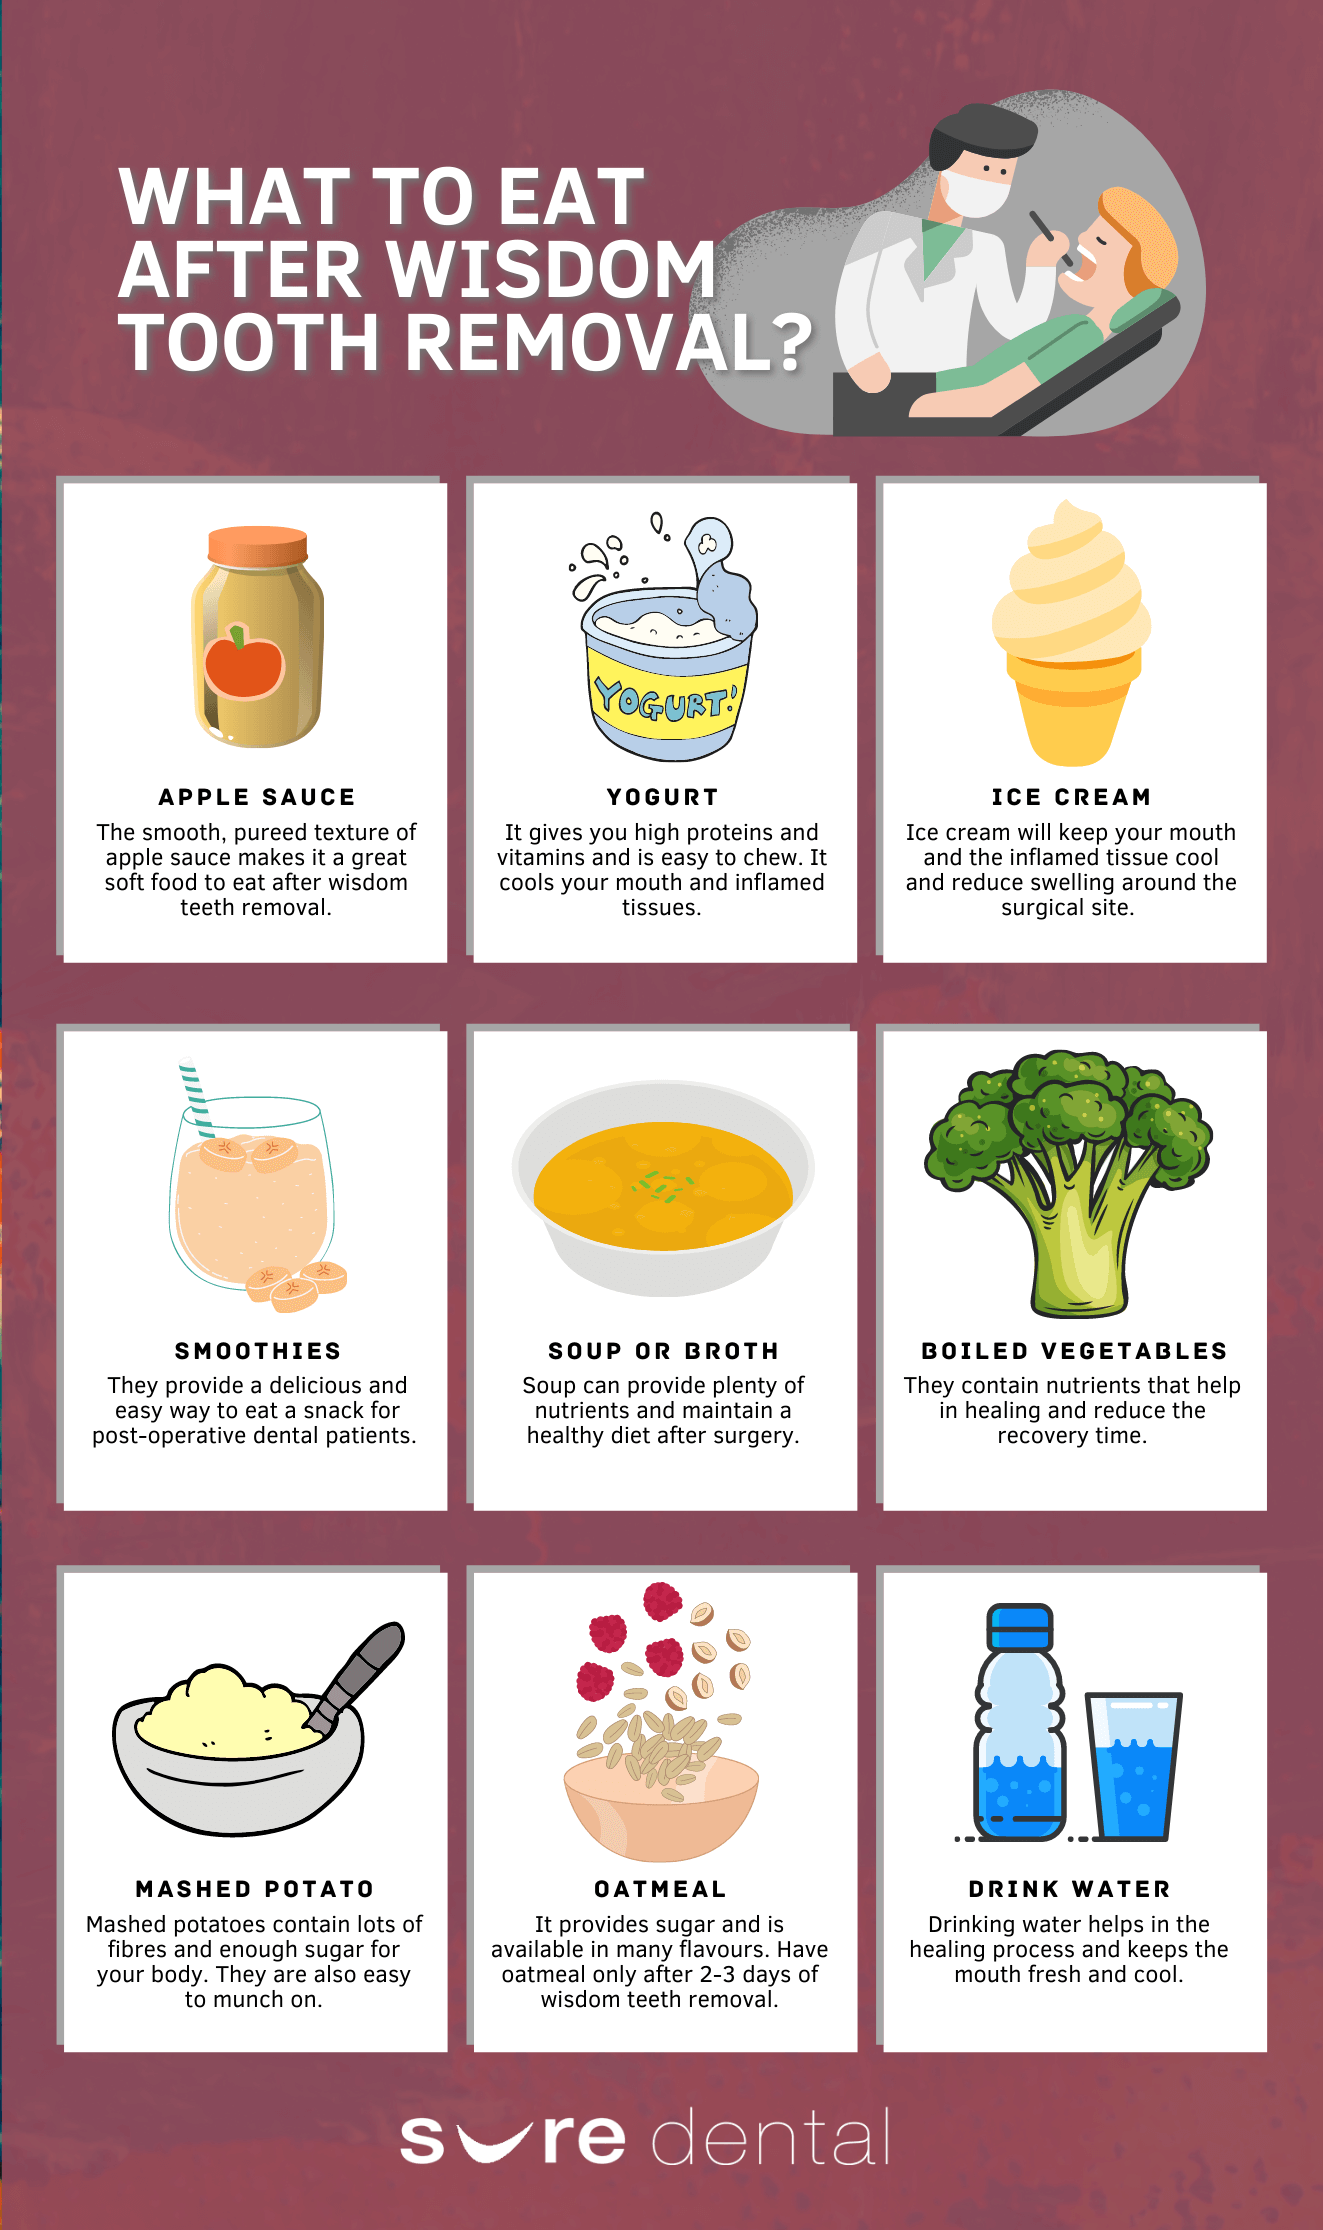

When Can You Eat Solid Foods After Wisdom Tooth Extraction Dr Alex

When Can You Eat Solid Foods After Wisdom Teeth Removal

When Can I Eat Solid Food After Wisdom Teeth Removal Wisdom Teeth

When Can You Eat Solid Foods Again After Wisdom Teeth Removal Jinny Doe

When Can I Eat Solid Food After Wisdom Teeth Removal Wisdom Teeth

When Can I Eat Solid Food After All Wisdom Teeth Removal

What To Eat After Wisdom Teeth Removal Sure Dental

What To Eat After Wisdom Teeth Removal Sure Dental